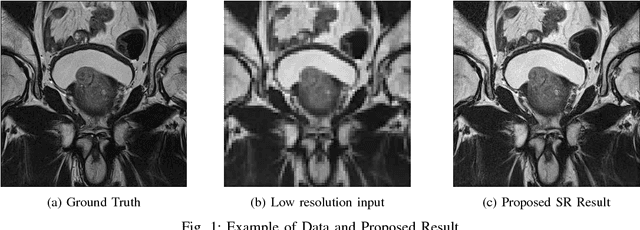

Abstract:Acquiring High Resolution (HR) Magnetic Resonance (MR) images requires the patient to remain still for long periods of time, which causes patient discomfort and increases the probability of motion induced image artifacts. A possible solution is to acquire low resolution (LR) images and to process them with the Super Resolution Generative Adversarial Network (SRGAN) to create an HR version. Acquiring LR images requires a lower scan time than acquiring HR images, which allows for higher patient comfort and scanner throughput. This work applies SRGAN to MR images of the prostate to improve the in-plane resolution by factors of 4 and 8. The term 'super resolution' in the context of this paper defines the post processing enhancement of medical images as opposed to 'high resolution' which defines native image resolution acquired during the MR acquisition phase. We also compare the SRGAN to three other models: SRCNN, SRResNet, and Sparse Representation. While the SRGAN results do not have the best Peak Signal to Noise Ratio (PSNR) or Structural Similarity (SSIM) metrics, they are the visually most similar to the original HR images, as portrayed by the Mean Opinion Score (MOS) results.

Abstract:Acquiring High Resolution (HR) Magnetic Resonance (MR) images requires the patient to remain still for long periods of time, which causes patient discomfort and increases the probability of motion induced image artifacts. A possible solution is to acquire low resolution (LR) images and to process them with the Super Resolution Generative Adversarial Network (SRGAN) to create a super-resolved version. This work applies SRGAN to MR images of the prostate and performs three experiments. The first experiment explores improving the in-plane MR image resolution by factors of 4 and 8, and shows that, while the PSNR and SSIM (Structural SIMilarity) metrics are lower than the isotropic bicubic interpolation baseline, the SRGAN is able to create images that have high edge fidelity. The second experiment explores anisotropic super-resolution via synthetic images, in that the input images to the network are anisotropically downsampled versions of HR images. This experiment demonstrates the ability of the modified SRGAN to perform anisotropic super-resolution, with quantitative image metrics that are comparable to those of the anisotropic bicubic interpolation baseline. Finally, the third experiment applies a modified version of the SRGAN to super-resolve anisotropic images obtained from the through-plane slices of the volumetric MR data. The output super-resolved images contain a significant amount of high frequency information that make them visually close to their HR counterparts. Overall, the promising results from each experiment show that super-resolution for MR images is a successful technique and that producing isotropic MR image volumes from anisotropic slices is an achievable goal.